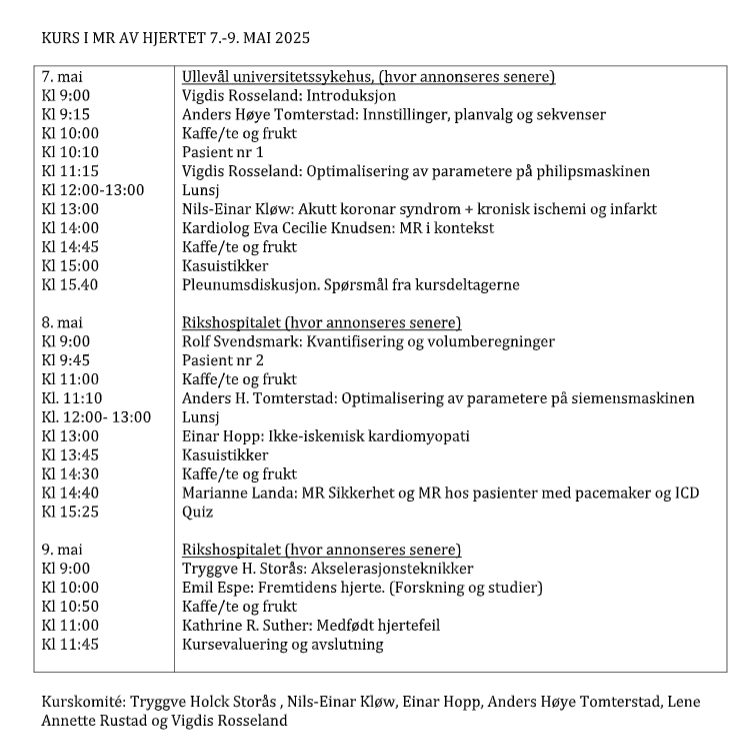

1. dag Ullevål universitetssykehus

2. og 3 dag: Rikshospitalet